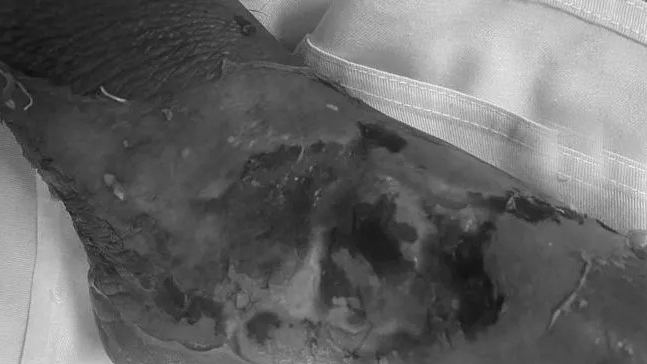

Bệnh nhi được người nhà đưa đến Bệnh viện Đa khoa Hùng Vương (Phú Thọ) trong tình trạng quấy khóc, vùng bỏng 2 bàn chân sưng nề chảy dịch đục, trợt da, từ cổ chân đến các ngón chân da bẩn, nhựa lá cây dính bết vào vết bỏng, hai bàn chân nhiễm trùng nặng, cử động cổ chân hạn chế.

Người nhà bệnh nhi cho biết, bé vô tình cho cả hai chân vào chậu nước sôi vừa rót ra chậu. Ở nhà, bé được điều trị bằng đắp thuốc nam nhưng sau đó bé quấy khóc, sốt, vết bỏng chảy dịch đục, bé không ăn, bàn chân sưng nề nên gia đình đưa bé đến bệnh viện khám.

Bác sĩ xác định: Bệnh nhi bị bỏng ở mức độ II, III nếu sau khi bị bỏng đến bệnh viện xử lý vết thương ngay thì thời gian phục hồi sẽ nhanh chóng, tránh các biến chứng nguy hiểm. Nhưng do không được điều trị đúng cách, bệnh nhi hiện tại bị nhiễm trùng nặng hai bàn chân, nguy cơ nhiễm trùng huyết và có thể nguy hiểm đến tính mạng bất cứ lúc nào.

Các bác sĩ cảnh báo về tình trạng nhiễm trùng nặng vết bỏng do đắp lá thuốc điều trị, nhưng vẫn còn rất nhiều người quá tin tưởng vào tác dụng kỳ diệu của đắp lá thuốc. Có những bệnh nhân vùng bỏng đã hoại tử sâu, phải ghép da rất phức tạp, để lại nhiều di chứng cho bệnh nhân cũng như thời gian điều trị kéo dài.